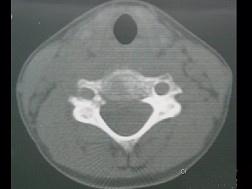

问题 男,37岁,主诉颈部疼痛,活动时加重,休息后疼痛可减轻,夜间盗汗等,请结合所提供图像,选出最佳答案 ( )

选项 A、颈椎结核 B、骨髓瘤 C、颈椎骨转移 D、颈椎退行性变 E、骨巨细胞瘤

答案 A